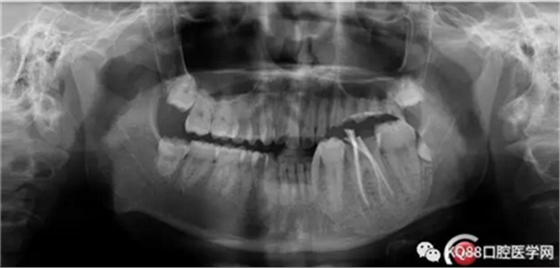

第四步:試尖片。四個根管,錐度良好,牙膠尖到位。

第五步:充填完成,ZOE暫時觀察。